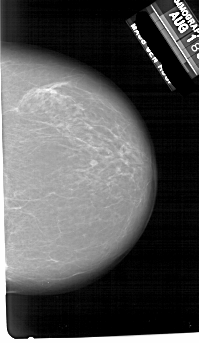

A_1649_1.LEFT_MLO

LEFT_MLO LINES 6466 PIXELS_PER_LINE 3751 BITS_PER_PIXEL 12 RESOLUTION 43.5 OVERLAY